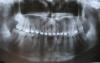

Асия Опубликовано 23 июля, 2010 Поделиться Опубликовано 23 июля, 2010 Вот снимок,что можете сказать по моей ситуации? Возможна ли имплантация?, нужно ли наращивать десну?. Ссылка на комментарий

DShu Опубликовано 23 июля, 2010 Поделиться Опубликовано 23 июля, 2010 1) снимки неинформативны, перефотографируйте2) фото в полости рта3) уточните вопрос (десну/кость) Ссылка на комментарий

Асия Опубликовано 25 июля, 2010 Автор Поделиться Опубликовано 25 июля, 2010 1) снимки неинформативны, перефотографируйте2) фото в полости рта3) уточните вопрос (десну/кость)Ну не знаю как еще лучше сфоткать, в принципе видно так же как на снимке. Разве не видно?Ну я имею ввиду надо ли наращивать,чтоб имплантант вставить или так достаточно. Ссылка на комментарий

Bier Опубликовано 25 июля, 2010 Поделиться Опубликовано 25 июля, 2010 значит сделайте цифровую ортопантомограмму и выложите сразу файл на форум, через радикал. + надо фото из полости рта. Ссылка на комментарий